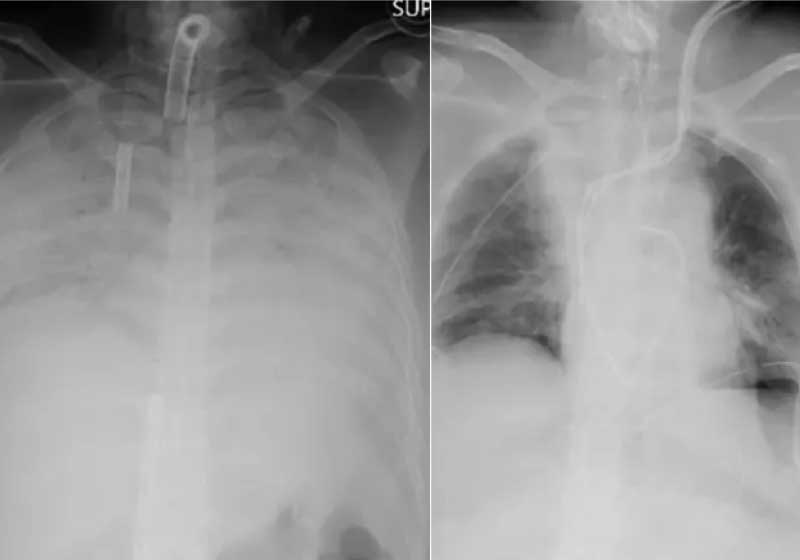

Uma mulher que teve sérias complicações respiratórias recebeu o 1º transplante de tecido pulmonar de doador vivo em pacientes com Covid-19.

De acordo com o hospital, este caso foi o primeiro em que um tecido pulmonar foi transplantado de doadores vivos para um paciente com Covid-19. O sucesso do procedimento trouxe esperanças para pessoas que ficaram com sequelas da doença.

As complicações levaram a paciente a ficar por meses em uma máquina que funcionava como um pulmão artificial, de acordo com o Hospital da Universidade de Kyoto.

A covid deixou sequelas fortes no pulmão da mulher, a ponto de o órgão não funcionar mais sem apoio de um aparelho.

Dr. Hiroshi Date, cirurgião torácico do hospital que conduziu a operação, disse que o sucesso da cirurgia deu esperança aos pacientes que sofrem de graves danos pulmonares causados pela Covid-19.

“Demonstramos que agora temos a opção de transplantes de pulmão (de doadores vivos)”, disse ele em entrevista coletiva na última quinta-feira.